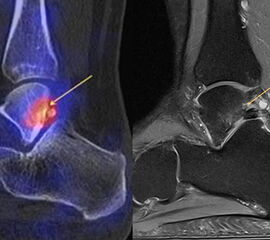

Abbildung 8.1. a bis f.: Patient mit Z. n. OSG-Distorsion vor 8 Monaten und konservativer Therapie. Anhaltende Schmerzen im Bereich des linken Innenknöchels. Im MRT bestand der Verdacht auf eine symptomatische kleine osteochondrale Läsion im medialen linken Talus (Abbildung 8.1. a und c). Zur weiteren Klärung erfolgte eine SPECT/CT 30 Tage später, welche jedoch im Gegensatz zur MRT eine fokale Mehrspeicherung an der tibialen Insertion des Deltabandes nachwies. Die Tatsache, dass die SPECT/CT spezifischer als die MRT symptomatische Bandläsionen detektieren kann wird untenstehend ausführlich thematisiert.

Abbildung 8.2. zeigt den Fall eines Patienten mit Verdacht auf ein knöchernes posteriores Impingement. Es bestanden Beschwerden dorsal bei Plantarflexion und ein Z. n. Distorsion des linken OSG vor 2,5 Jahren. Im MRT 2 Monate vor der SPECT/CT keine wegweisenden Befunde. Im SPECT/CT eindeutige fokal deutliche Mehrspeicherung im Bereich des Processus posterior tali.